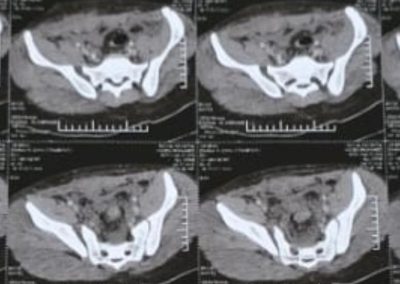

ياسين محمد أمين العمر:١٧ عامًا اصيب بكسر غير ثابت متفتت بالحوض يناير ٢٠٢٣